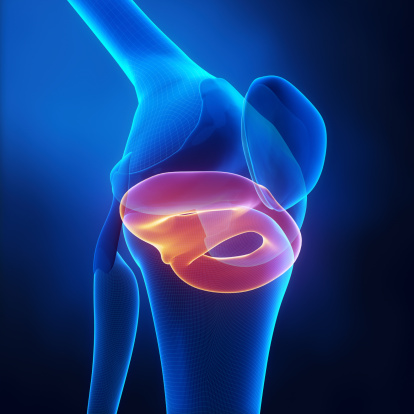

무릎 퇴행성 관절염은 무릎 관절을 보호하고 있는

연골이 다양한 원인에 의해 손상되거나 닳아

없어져 통증이 오는 상태입니다.

1. 운동을 하다 무릎내의 연골이나 반월상연골판

손상을 방치하는 경우.

줄기세포는 신경, 혈액, 연골 등의 여러 세포들로

분화가 가능하며 재생 기능을 가진 세포로

이 기능을 이용하여 연골 손상부위에 이식하여

치료할 수 있습니다.

이를 통해 닳아 없어진 관절연골을 대체하는 것이

가능합니다.